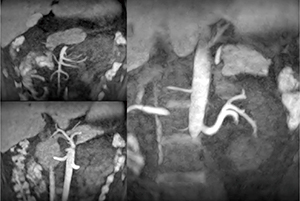

非造影MRA撮像は,さまざまな手法の開発とともに適応領域を大幅に広げてきた。腹部領域においては,特にASL法を応用したTime-SLIP法により血管を選択して描出することが可能となり,さらに血液の流れを利用した撮像法のため,血流の方向性なども観察できるようになった。しかし,血流動態を把握したい場合,Time-SLIP法は1回の撮像で1つの血流時相しか描出できないため,撮像を複数回繰り返す必要があり検査として非常に困難であった。そこで誕生したのが,ASLとlook-lockerサンプリングを組み合わせた“mASTAR法”である。mASTAR法では一度のラベリングで複数時相のデータを収集できるため(図1 a),1回の撮像で撮像時間を延長することなく血流動態の観察を可能とする(図1 b)。また,近年では,ultrashort TE(以下,UTE)法とASL法やmASTAR法を組み合わせた撮像も用いることが可能となっている。UTE法は,位相エンコード傾斜磁場を用いずにRF 励起パルスのすぐ後からデータ収集を行うため,非常に短いTEでの撮像が可能なシーケンスである。そのため,血流の速い部分や金属の影響による信号低下を抑えることができる。頭部領域ではすでに臨床活用されており,ステントやクリップ留置部の描出向上が報告されている。腹部領域においても,術後のフォローアップなどで同様の適応が期待され,検査適応の幅がさらに広がるものと考えられる(図2)。

図2 UTE法を用いた腎動脈の画像